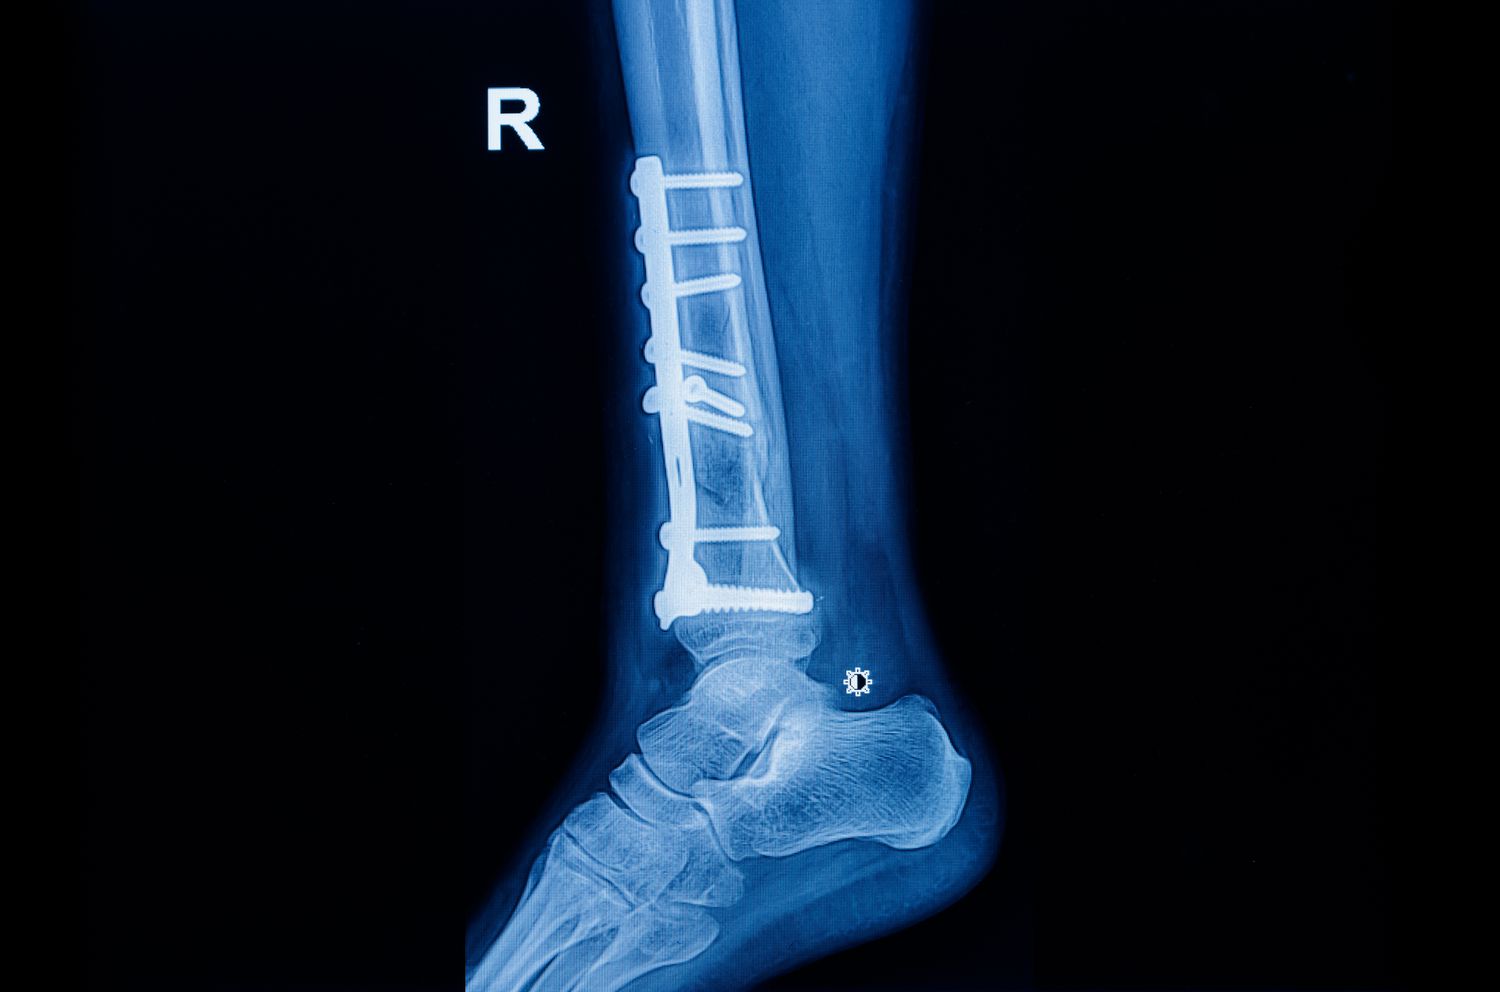

Sometimes, the X-ray looks worse than the outcome. A patient with a crushed lower leg discovered that the metal implant fixing his broken bones had bent months after surgery. He blamed the doctors for using substandard material and filed a complaint, but the court found the treatment had been textbook-perfect.

Over the next few months, the patient attended regular follow-ups. By December, the fracture site had aligned well and X-rays showed proper healing. But by the end of that month, one image revealed a slight bend in the implant. The patient claimed it was due to faulty fixation or poor-quality material, and alleged that the doctors suppressed the problem. He later underwent further care at another hospital, and approached the consumer forum demanding compensation for medical negligence.

The Kerala State Commission agreed. It observed that the failure occurred nearly five months after fixation, by which time the patient was already mobile. It accepted the expert’s opinion that such implant stress is possible in compound fractures and doesn’t imply defective equipment or poor surgery. The earlier order of negligence was set aside, and the doctors were cleared.